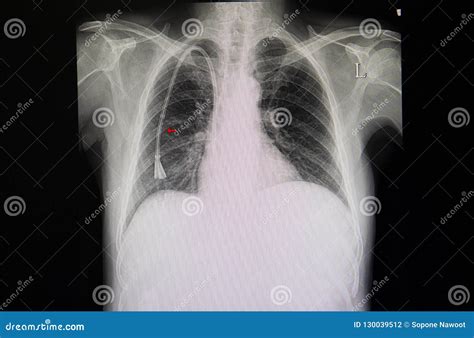

A chest catheter for dialysis, often medically referred to as a tunneled central venous catheter (CVC), is a flexible, hollow tube inserted into a large vein, typically the internal jugular vein in the neck. The tube is “tunneled” under the skin of the chest wall before it enters the vein, which helps stabilize the device and reduces the risk of infection. These catheters are generally used when a patient needs immediate dialysis access before a permanent fistula or graft is mature enough to be used, or when other forms of vascular access are not currently viable.

• Tunneled Catheters: The most common chest catheter for dialysis for long-term bridge therapy. They include a cuff that anchors the catheter under the skin, promoting tissue growth that provides a physical barrier against bacteria.